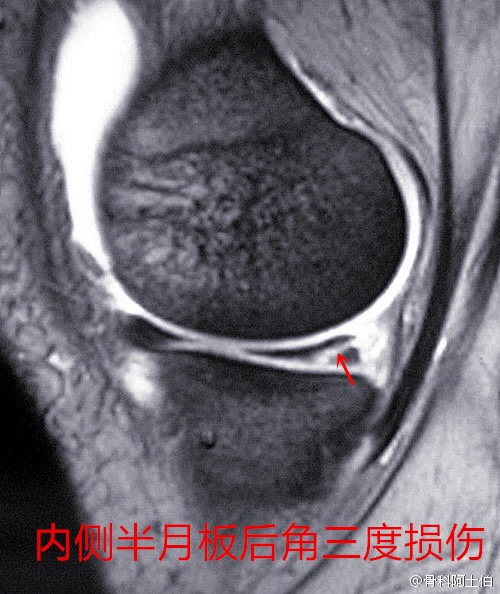

右膝关节内侧半月板后角损伤,膝关节伸直疼痛

300x276 - 56KB - PNG

膝半月板损伤,服用氨糖无效! 建议到正规三甲医院骨科检查,可以做膝关节CT检查,核磁检查,关节镜检查等。看一下半月板的损伤程度,明确诊断,对症治疗,局部可以热敷烤电等物